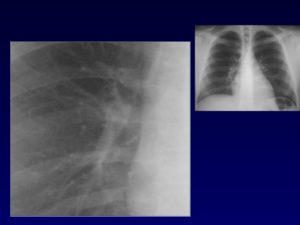

Тяжистые корни символизирует начало хронического или остро – воспалительного процесса. Чаще всего причиной подобного отклонения становятся профессиональные или затяжные заболевания. На рентгенограмме они выглядят «зубчатыми» и плотными, это объясняется тем, что увеличился объем соединительной ткани.

Тяжистые и усиленные корни

Этот термин означает, что в лёгких может происходить как острый, так и хронический процесс. Чаще всего это связывают с профессиональными заболеваниями (например, асбестоз) или с хроническими (например, бронхит курильщика).

На рентгенограмме тяжистые корни выглядят более плотными и неровными, это объясняется увеличением количества соединительной ткани — тяжей.